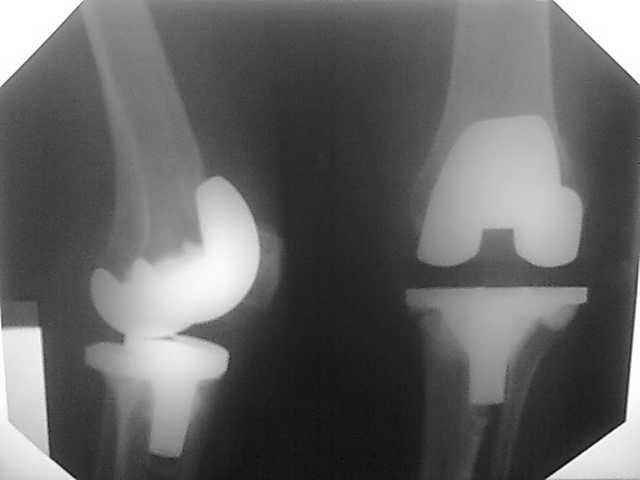

стабилизатором. В октябре 2008 - нестабильность, свищ. В другом стационаре все удалено,

спейсер с гентамицином, длинный курс антибиотиков.

Коллатеральных связок нет. Собственная связка надколенника цела. До удаления протеза -

выраженная смешанная контрактура. Сейчас свищей нет, анализы в порядке. Планы: Стоит выбор

Имя     : 3-21.08.08.jpg

Тип     : image/jpeg

Размер  : 16133 байтов

Описание: отсутствует

Url     : http://weborto.net:8080/pipermail/ortho/attachments/20090219/242fe889/attachment-0008.jpg